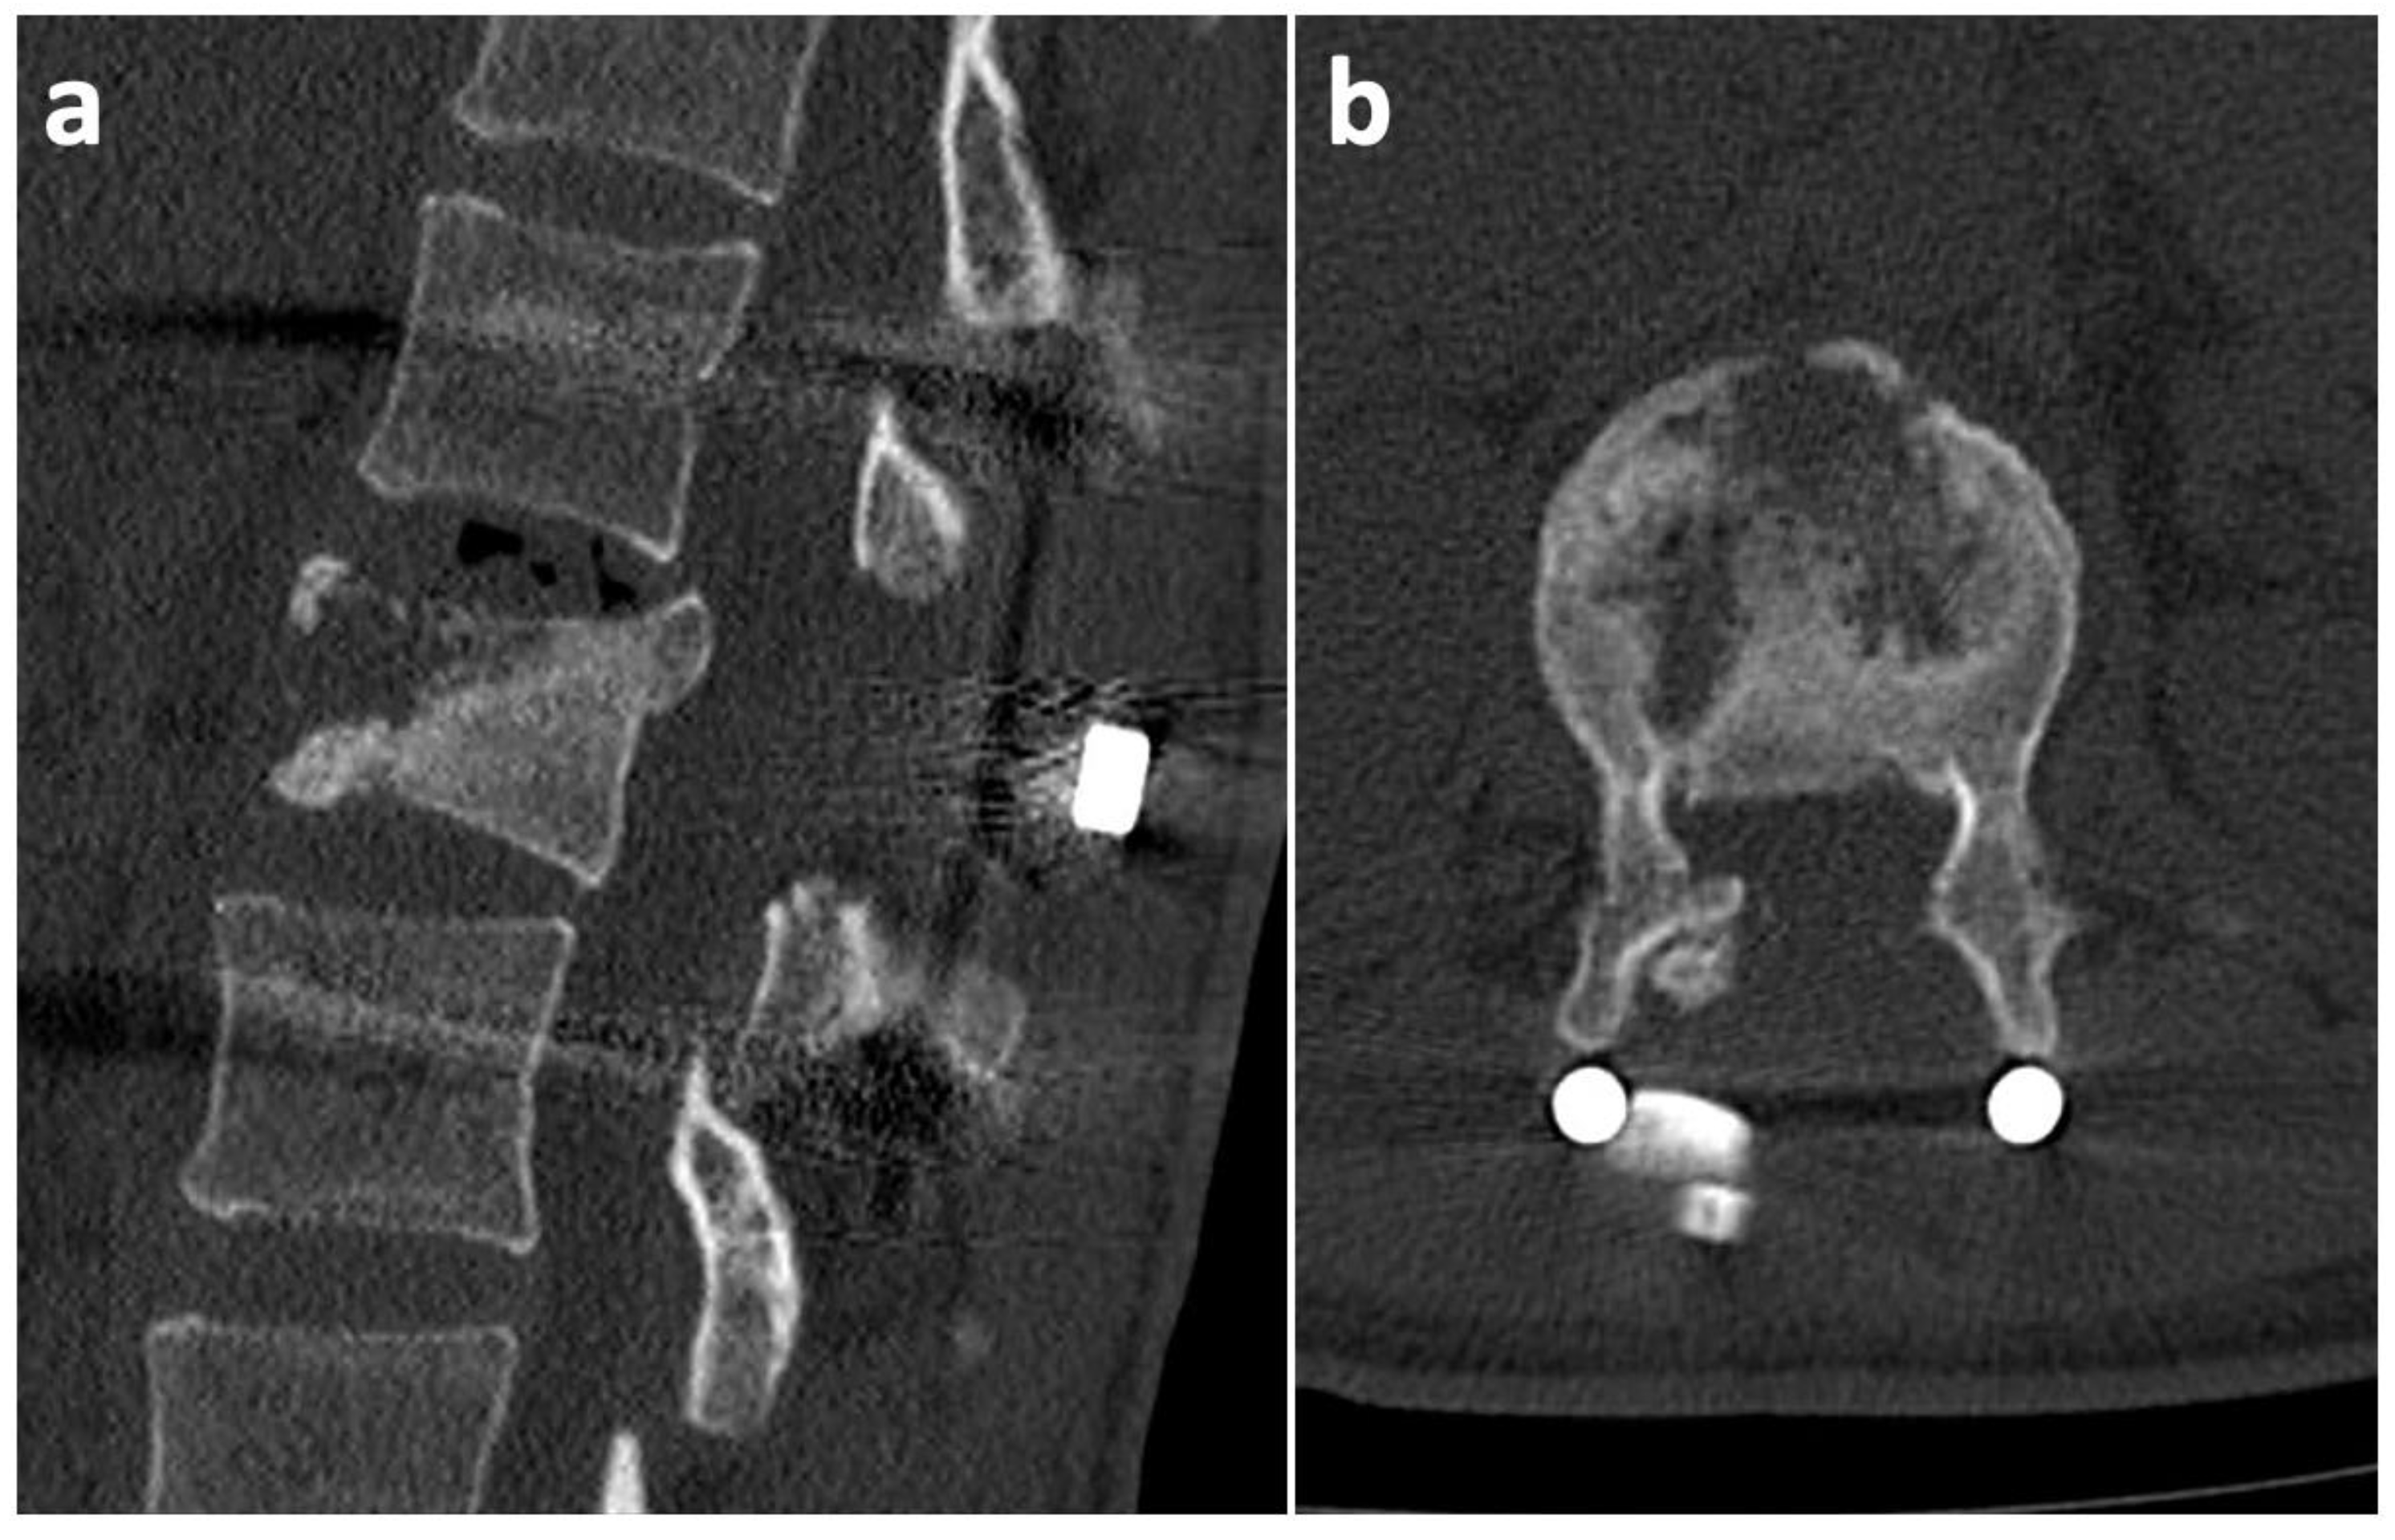

2. Case History